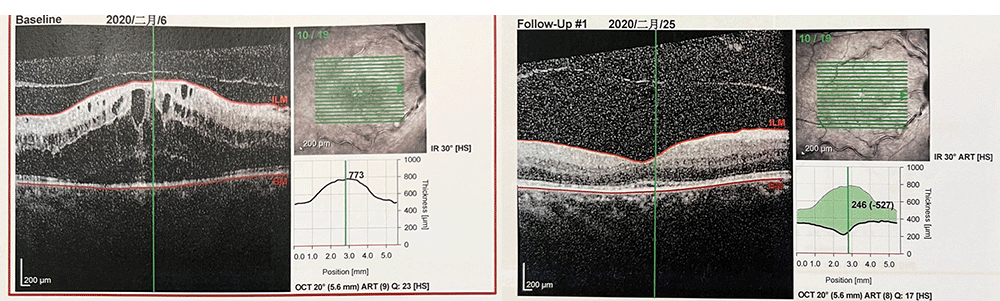

• 2020年2月11日:行右眼抗VEGF治疗(雷珠单抗)

第1次抗VEGF治疗后13天,2020年2月25日

自觉视力有提高

视力:VOD 0.8

眼压:15mmHg

嘱其1个月后复查

雷珠单抗10次注射CRT趋势

2020.2.6-11.24共注射雷珠单抗10针,每次注射后CRT均有不同程度消退,但每次25天左右即复发至800-1000um,视力则在小数视力0.8-0.1之间波动,末次随访视力为0.2。

整体趋势来看患者CRVO-ME治疗效果在下降